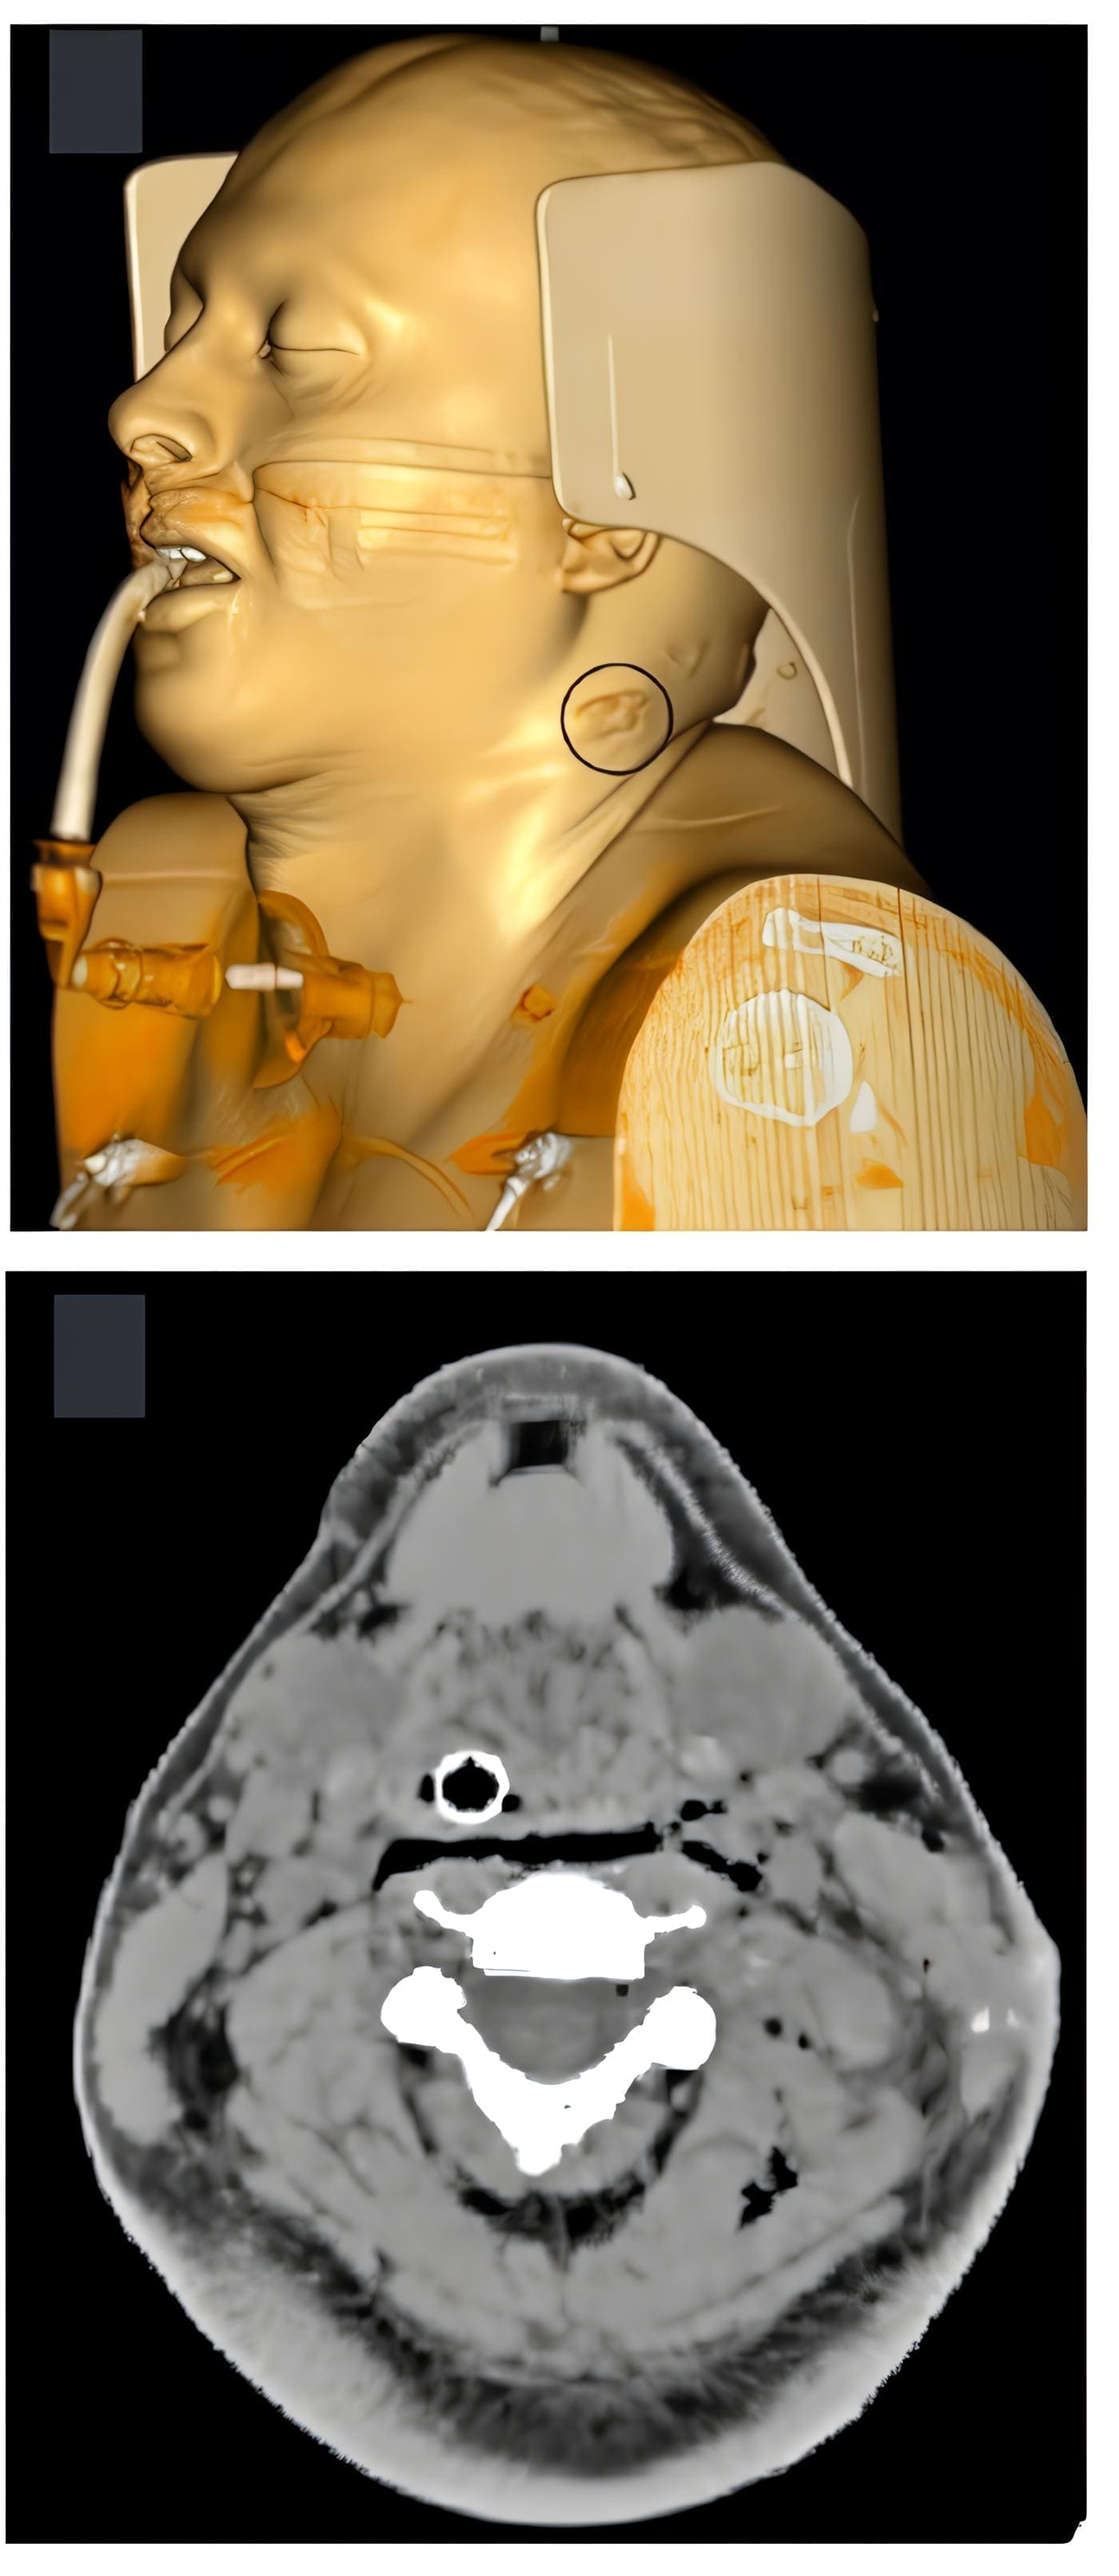

Por tratarse de un trauma cervical con aparente trayectoria transcervical, en un paciente estable hemodinámicamente, con un signo de sospecha de lesión vascular, e imposibilidad de valoración sintomática por la sedación e intubación orotraqueal, se decidió realizar una angiotomografía de cuello donde reportaron leve enfisema retrofaríngeo, laríngeo y en planos musculares (Figura 1).

Figura 1. Imágenes axiales de TC simple y contrastada del cuello. A. En la fase simple se identifica un cuerpo extraño con morfología redondeada (asterisco), hiperdenso (700 UH en promedio), de localización intramuscular paravertebral izquierda en cuello. B. En fase arterial se corrobora la integridad de las arterias carótidas comunes (flechas) y vertebrales (puntas de flecha). C. Al igual se observan las estructuras venosas, como las yugulares internas (flechas), sin presentarse evidencia de sangrado activo. Fuente: propia.

La tomografía descartó trayecto transcervical, lesión vascular, ósea, nerviosa o de órganos y se identificó un proyectil de caucho (proyectil de energía cinética) alojado en masa muscular paravertebral, con proximidad al musculo elevador de la escapula del lado izquierdo.

Debido a la sospecha de lesión de la vía aérea por la presencia de gas en el espacio visceral (Figura 2), se practicó una fibrobroncoscopia, que mostró adecuada movilidad de los pliegues vocales, sin lesiones supraglóticas, glóticas o traqueales.

Figura 2. Enfisema presente en los tejidos blandos superficiales y profundos del lado izquierdo del cuello (incluyendo espacios retrofaríngeo y carotideo, no correspondiente a la herida por el proyectil, el cual ingresó en la zona II del hemicuello izquierdo (circulo negro) con vector postero-medial. Este enfisema probablemente fue iatrogénico por intubación traumática. Fuente: propia.